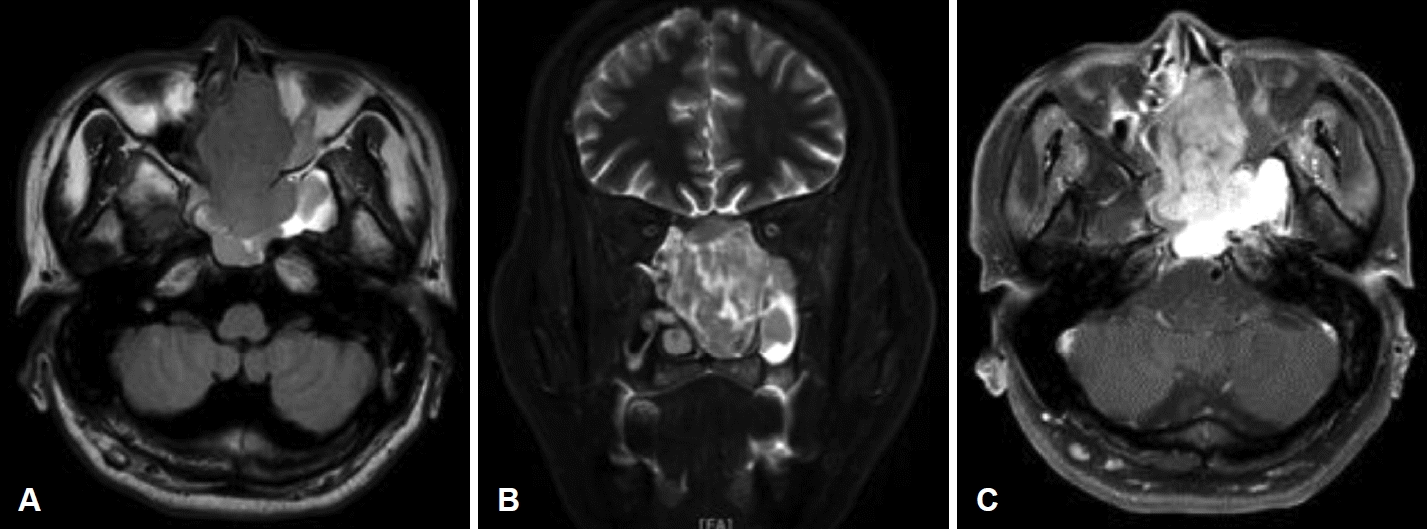

51세 남자 환자가 좌측 비강에서 발견된 종물을 주소로 본원 이비인후과에 내원하였다. 환자는 6개월 전 시작된 좌측 비출혈로 타병원을 처음 방문하였으며 우연히 좌측 비강에서 종물이 발견되어 본원으로 의뢰되었다. 환자는 지적장애 2급으로 일상적인 대화는 가능했으나 정확한 병력 청취에는 어려움이 있었다. 보호자에 의하면 환자는 비폐색과 비루를 호소하였으며 얼굴의 감각 이상이나 안구 건조증은 없었다. 신체 검사에서 피부에 밀크커피색 반점(cafe-au-lait spot)이나 국소 림프절 비대는 관찰되지 않았으며 과거력과 가족력상 특이사항은 없었다. 비내시경 검사상 광택이 나는 백색의 폴립양 종물이 좌측 비강을 가득 채우고 있었다(Fig. 1). 부비동 전산화단층촬영에서 좌측 비강에 약 7.4×5.2×5.3 cm 크기의 경계가 명확하고 조영증강이 잘되지 않은 종물이 관찰되었다. 종물 주변의 뼈는 얇아져 있었으나 골 침범의 소견은 없었으며 좌측 접형동, 사골동, 상악동에 부비동염이 의심되는 저밀도 음영이 관찰되었다(Fig. 2). 부비동 자기공명영상에서 종물은 T1 강조 영상에서 저신호 강도로 나타났으며 T1 조영증강 영상에서는 부분적으로 조영증강된 종물이 관찰되었다. 또한, T2 강조 영상에서는 종물이 고신호 강도로 나타났고 고리 모양의 구조가 고신호 강도로 나타나는 신경 다발 징후(fascicular sign)도 관찰되었다(Fig. 3). 종물에서 조직 생검을 시행하였으며 출혈은 심하지 않았다. 병리검사 결과 신경섬유종이 의심된다는 소견이 보고되었다.

Preoperative MRI images. A and B: The mass showed hypointense on axial T1-weighted image (A) and hyperintense on coronal T2-weighted image (B). C: Axial Gd-enhanced T1-weighted image revealed heterogeneous enhancement of the mass.